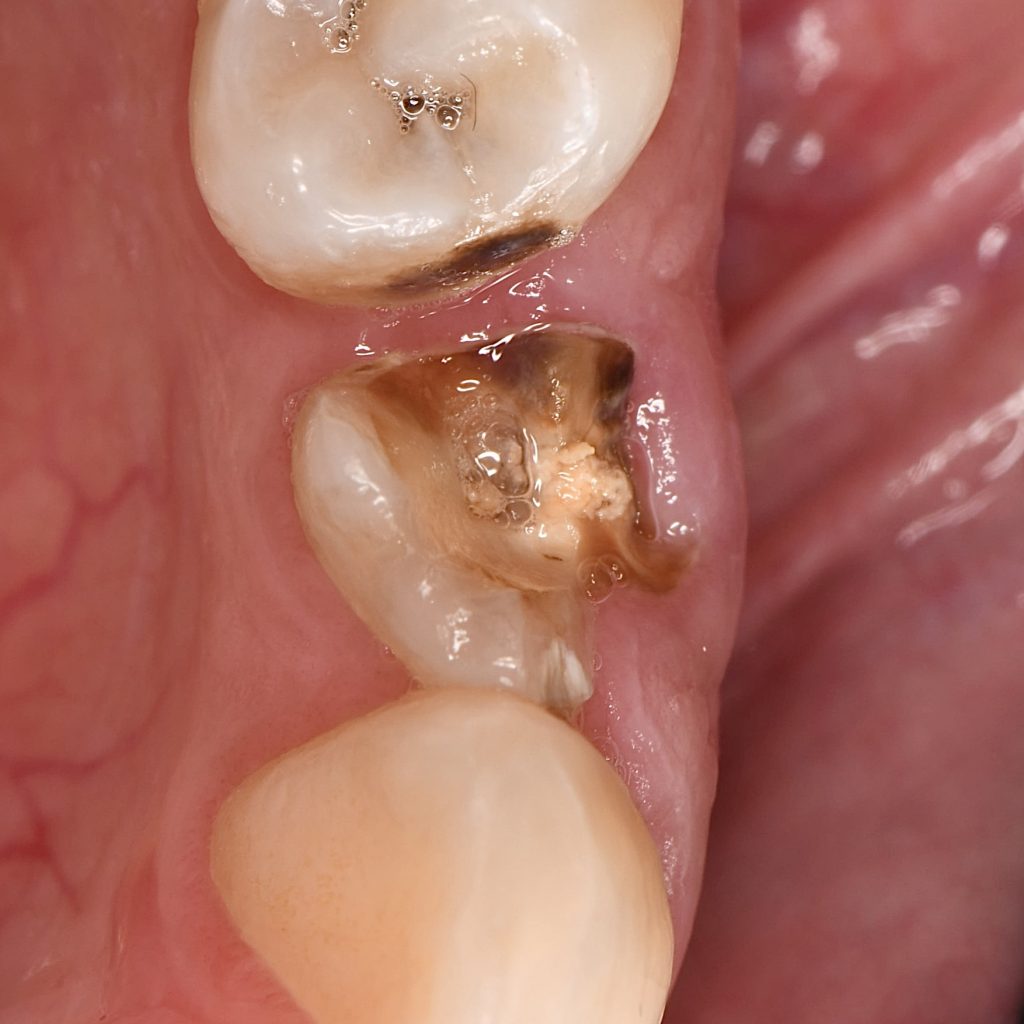

In this case, lower premolar ( 4) was treated previously with unsuccessful Endodontic treatment .

Initial situation